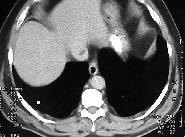

En las radiografías anteriores de tórax y abdomen simple así como en otros estudios de radiología no se observaron anormalidades. El médico tratante internista solicitó TAC abdominal en donde se demostró un defecto de llenado de la vena cava intra-hepática, el cual se identificó en varios cortes continuos, imagen persistente (Figura 1, 2).

Figura 1. Corte axial en hígado con defecto hipodenso en VCI. Hígado de aspecto normal.

Figura 2. Magnificación del corte en la figura 1. Imagen sospecha de trombo en VCI.

Se cuantificaron los coeficientes de absorción dentro de la lesión y se demostró que tenía unos coeficientes grasos -117 UH. (Figura 3). Con estos resultados se confirmó el diagnóstico de una variante anatómica consistente en colección grasa yuxta-cava. No se encontraron anomalías viscerales en el estudio realizado, con cambios degenerativos a nivel lumbo-sacro. No se efectuaron otros estudios adicionales y no hubo necesidad de otros exámenes complementarios como Doppler color o cavografía. (Figura 4)